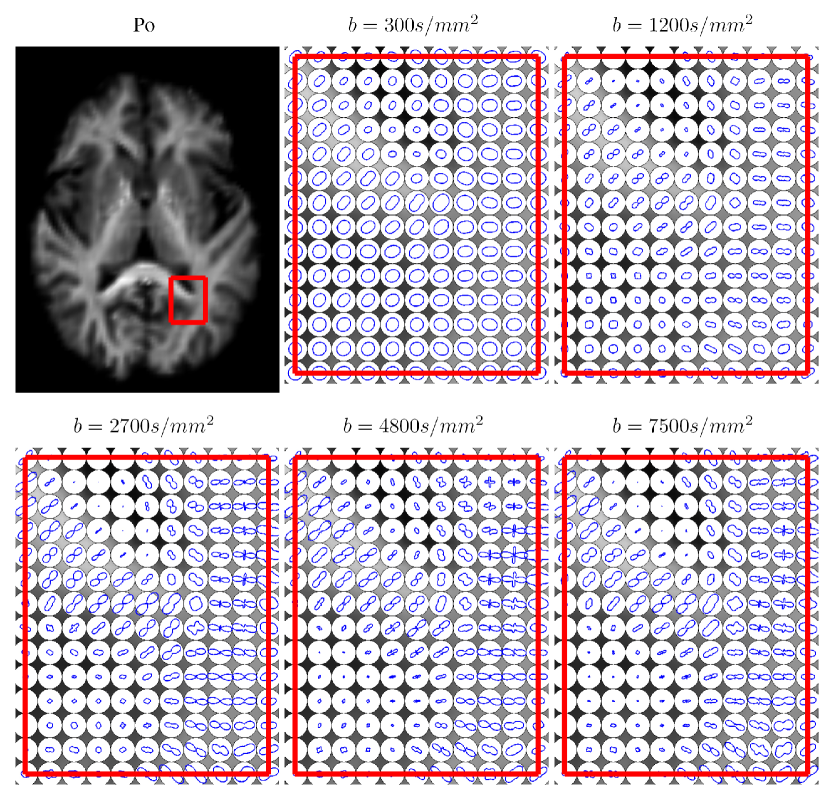

Next, we illustrate the atlas estimated from the 363636 adults’ HYDI datasets after ten iterations. Figure 2 illustrates the estimated atlas of the diffusion signals at shells of b=300,1200,2700,4800,7500​s/m​m2𝑏3001200270048007500π‘ π‘šsuperscriptπ‘š2b=300,1200,2700,4800,7500s/mm^{2}. Figure 3 shows the reconstructed EAP based on the coefficients of HYDI. Each row respectively shows the estimated atlas in the axial, coronal, and sagital views, while each column shows the zero displacement probability (Po) image derived from EAP and the diffusion profiles of this atlas at three layers of the EAP space. Figure 4 demostrates the estimated altas on the zero-displacement probability (Po), mean squared displacement (MSD), and generalized fractional anisotropy (GFA) under three different radii, as introduced in [14]. Visually, these figures show that the estimated atlas has the anatomical details of the brain white matter.

Figure 2: Illustration of the estimated HYDI atlas. The first panel shows the atlas of the zero displacement probability (Po) image in the axial view. The rest panels show the diffusion profiles in the region of interest (red frame) at individual shells with b𝑏b=300, 1200, 2700, 4800, and 7500 s/m​m2π‘ π‘šsuperscriptπ‘š2s/mm^{2} in the qπ‘žq-space. Note that the profile of the diffusion weighted signals is orthogonal to the fiber orientation.